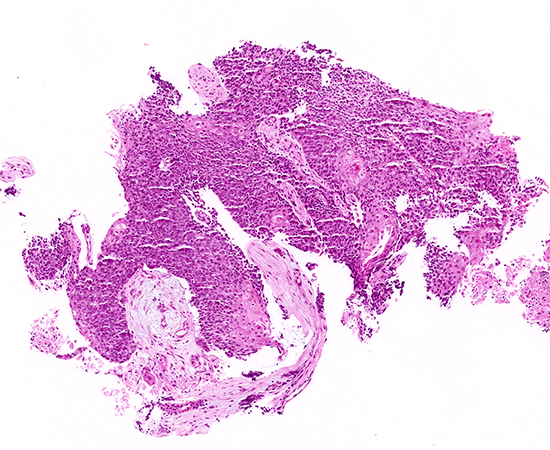

Clinical History:A man in his early 20s presented with progressive dyspnea and a cough producing mucus and tissue fragments. He is a non-smoker but has a history of occasional vaping. Imaging revealed a midline thoracic mass abutting the central airways with extensive mediastinal lymphadenopathy. A bronchoscopic biopsy was performed. The biopsy demonstrated sheets of tumor cells infiltrating a desmoplastic stroma (Figure 1, 4×). The neoplastic cells appeared relatively monotonous with focal keratinization (Figure 2, 10×; Figure 3, 20×). Notably, there were areas of abrupt squamous differentiation with keratin "pearls" (Figures 4 and 5, 20×). By immunohistochemistry, the tumor cells were diffusely positive for p40 and negative for TTF-1, and no intracytoplasmic mucin was identified on special stains. Given the patient's age and the unusual presentation, additional studies were performed: a NUT antibody immunostain showed speckled nuclear positivity, and molecular testing confirmed a BRD4::NUTM1 gene fusion, establishing the diagnosis.

Histologically, NUT carcinoma is characterized by sheets of monotonous, undifferentiated round to oval cells with scant cytoplasm, which may show abrupt foci of squamous differentiation (keratinization) amidst otherwise primitive cells. This abrupt keratinization—islands of maturing squamous cells within a sea of undifferentiated cells—is a pathognomonic clue that can suggest the diagnosis. The tumor generally lacks the overt pleomorphism seen in conventional smoking-related squamous carcinomas. In this case, the biopsy showed exactly those features: relatively uniform primitive cells with a few keratinizing nests.